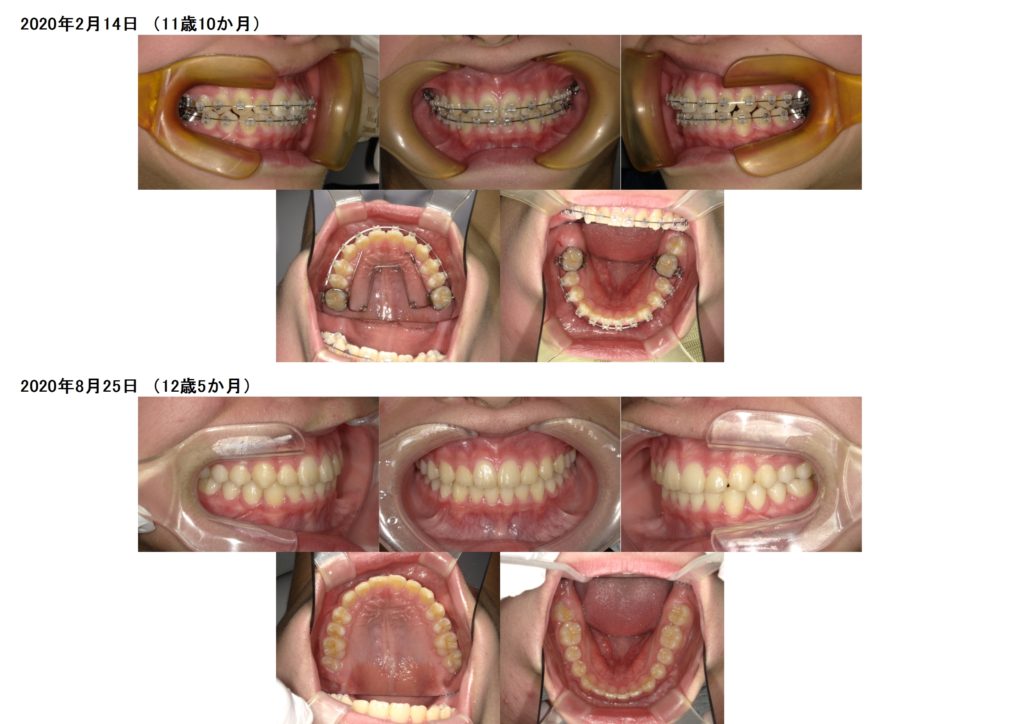

↑ジャ~ン!!外れました!!

↑治療前、治療後の写真です。

2年かからず、上下の顎を広げ、フルブラケットで治療が終わりました☆